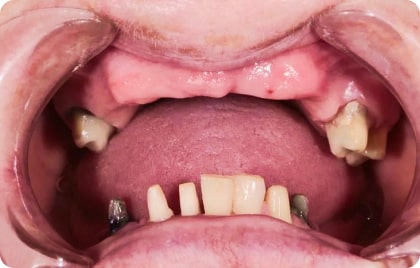

Зубы за 1 день от 7500₽ в месяц

Установка

за 1 день